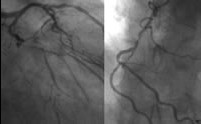

第三步:冠状动脉造影或直接PCI

经冠心病序贯性诊断程序第二步筛选确定行PCI或CABG的患者后,进入有创检查程序。CT-CA示冠状动脉病变较复杂的患者行CA后同时行PCI术或之后行CABG。而CT-CA示病变较孤立时,可选择直接行PCI。

图3 CA示LAD、RCA中远段闭塞